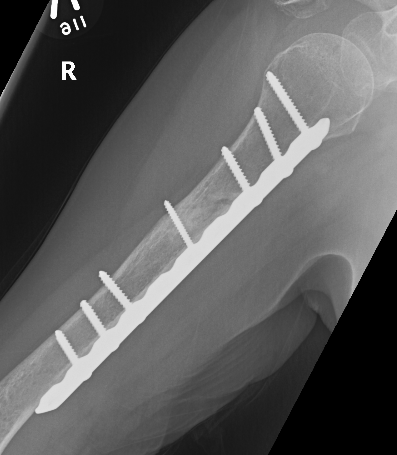

Humeral Fracture SegmentalHumeral Plate LateralHumeral Plate Long AP

Segmental fracture ORIF